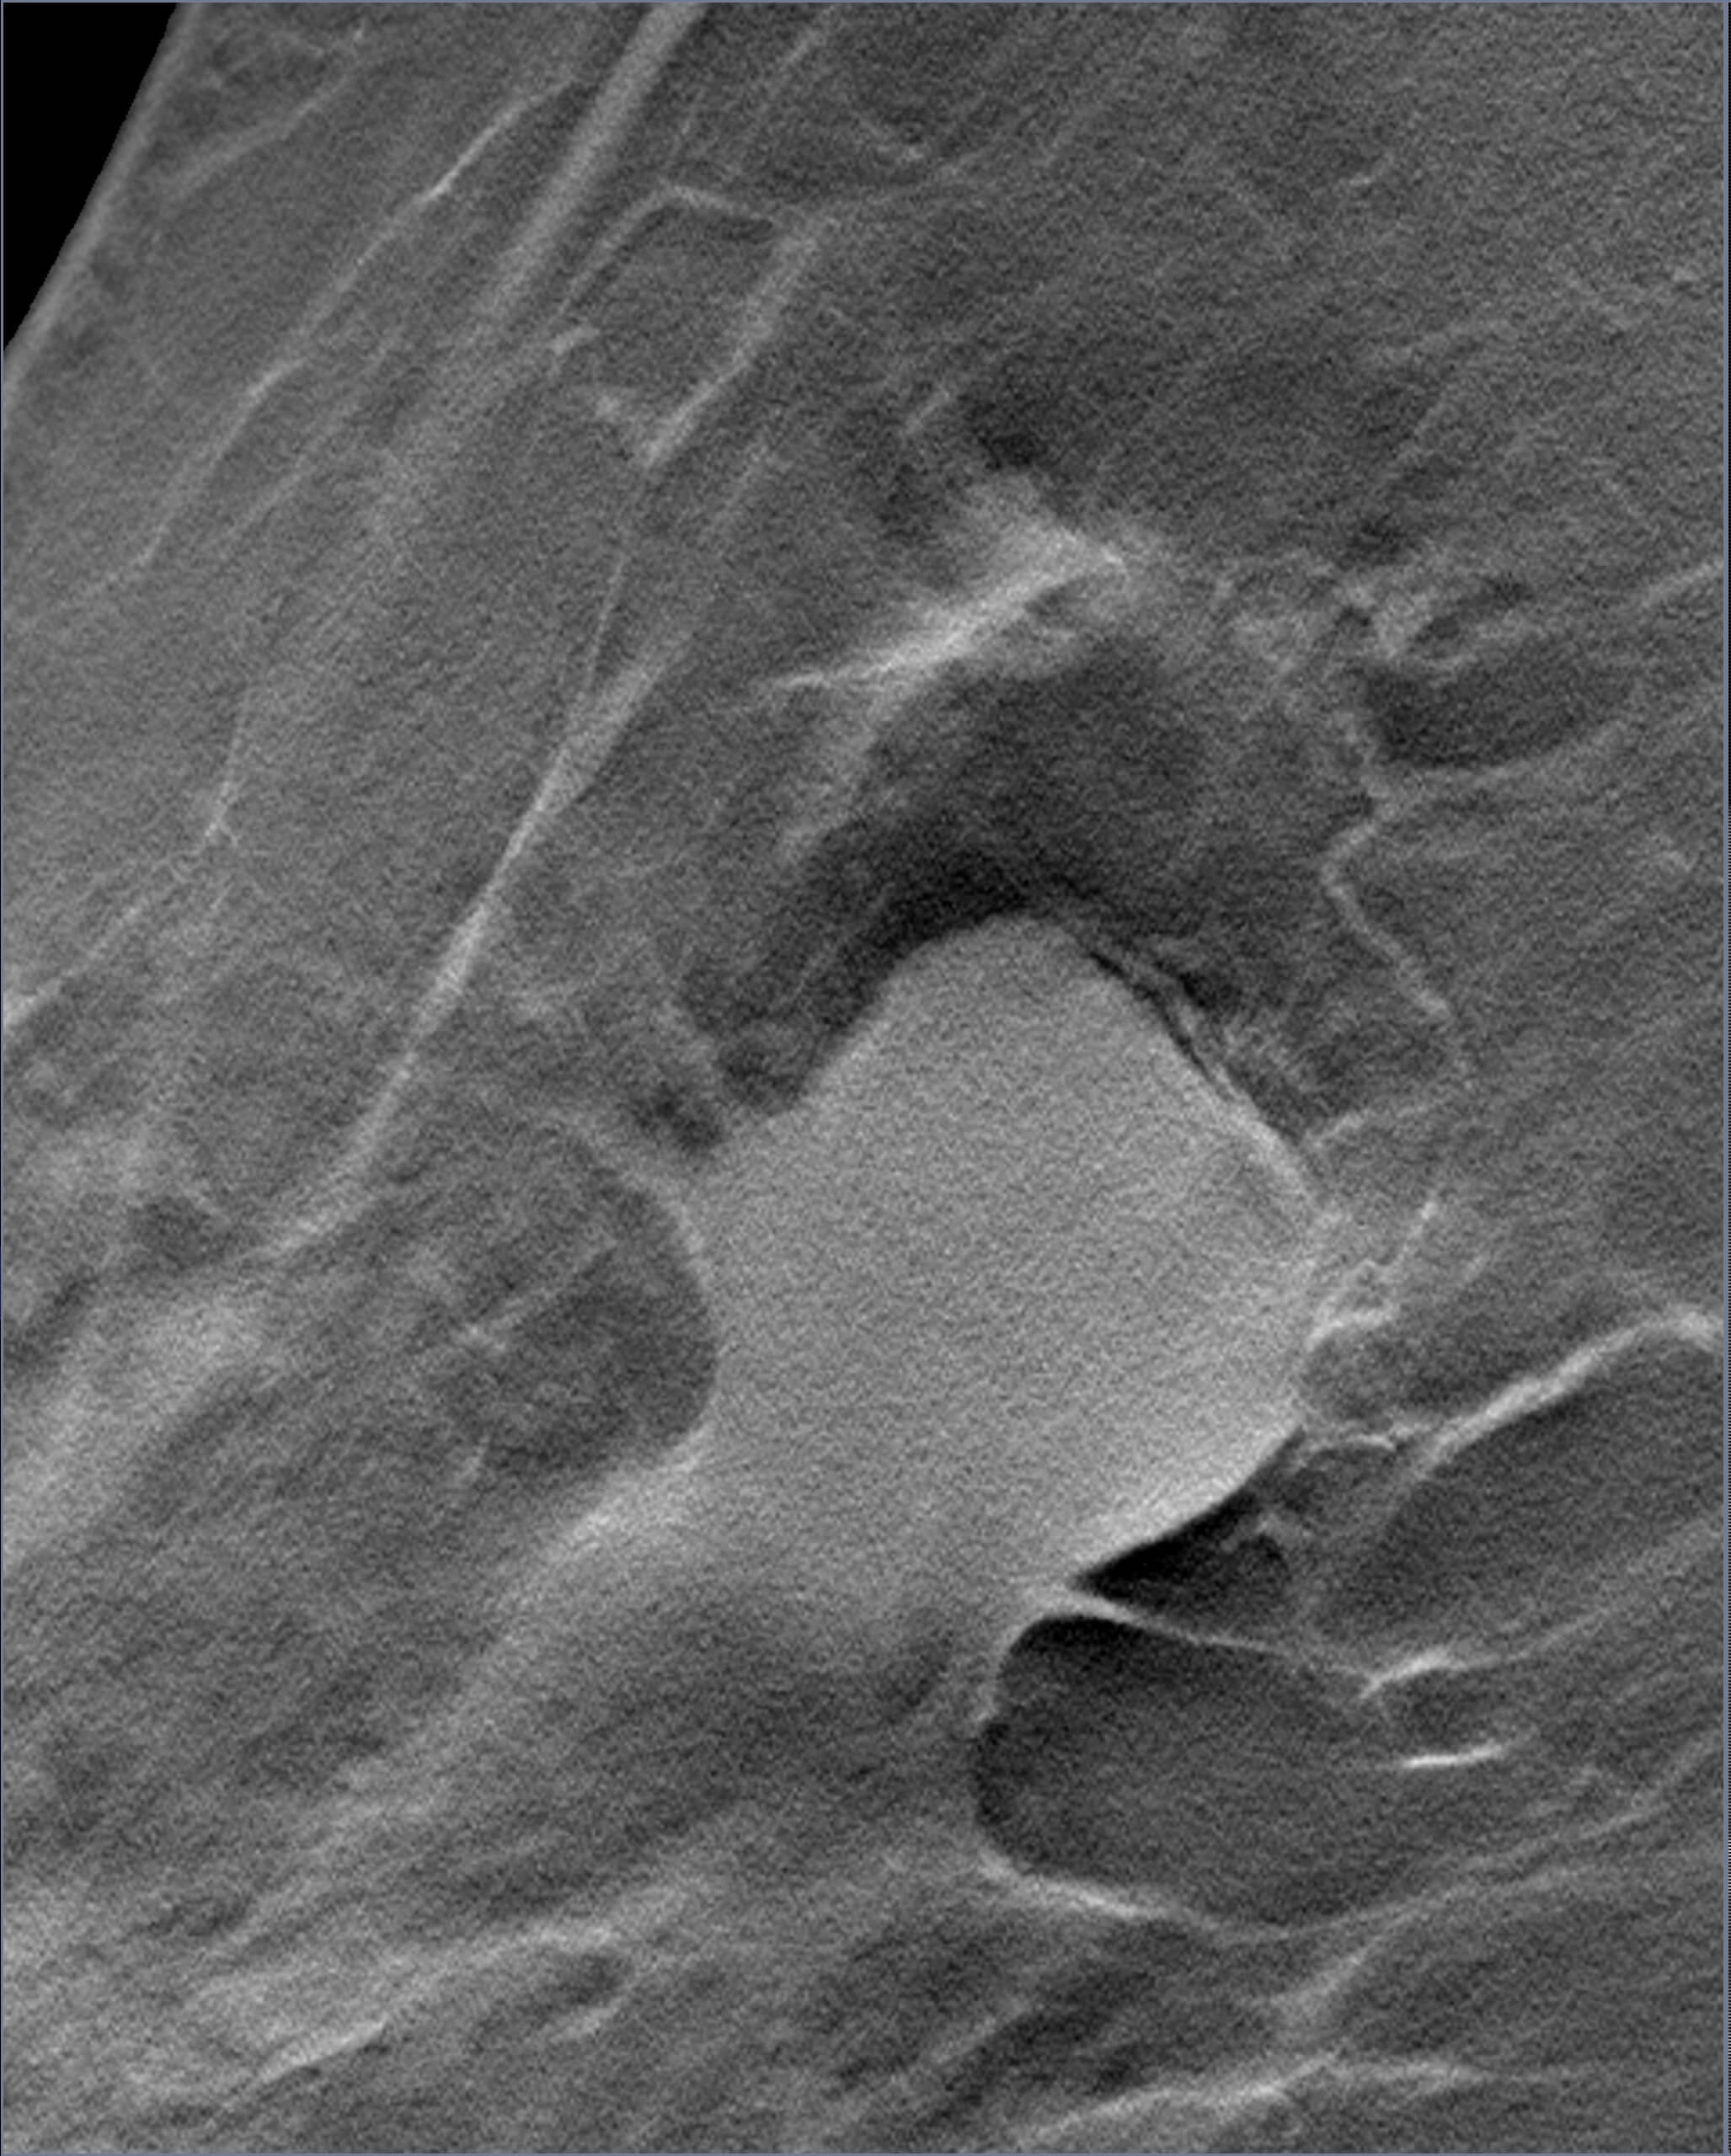

Mammogram revealed the presence of an irregular high density mass in the posterior third of the upper outer quadrant of the right breast with indistinct margins on two-dimensional mammogram. No internal calcification seen. No overlying skin thickening or retraction noted. DBT (Digital breast tomosynthesis) revealed the mass having spiculated margins and irregular shape. Corroborative ultrasound showed an irregular, heteroechoic solid mass at 10-11 O’clock position with anti-parallel orientation, microlobulated margins, posterior enhancement and internal necrotic/ cystic areas within. Mild internal vascularity was seen on color Doppler. No dilated ducts or intraductal extension was seen. No suspicious lymph nodes were present Further recommendation: Ultrasound guided core-needle biopsy with immunohistochemical analysis Management received: Right side lumpectomy with MRM Final histopathology: Metaplastic carcinoma (carcinosarcoma) with no nodal metastasis